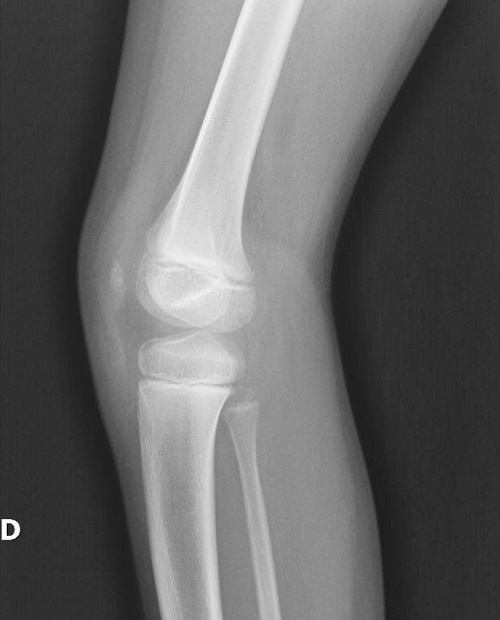

Posteriormente, se decide ampliar el estudio, realizándose radiografía de ambas rodillas, codos y caderas. En los resultados radiográficos se evidencia hipoplasia de ambas rótulas conocida sin luxación (Figuras 1 y 2). Se completa el estudio con resonancia magnética craneal sin hallazgos, y análisis de sangre y de orina para estudio de la función renal sin presentar alteraciones. Finalmente, se realiza estudio genético mediante secuenciación masiva NGS del gen LMX1B, encontrándose variante de significado incierto en LMX1B c.213C>G en heterocigosis. Posteriormente, se realiza un estudio genético en los progenitores, resultando negativo, concluyéndose que la variante es de novo.

Figura 1. Radiografía lateral de la rodilla derecha